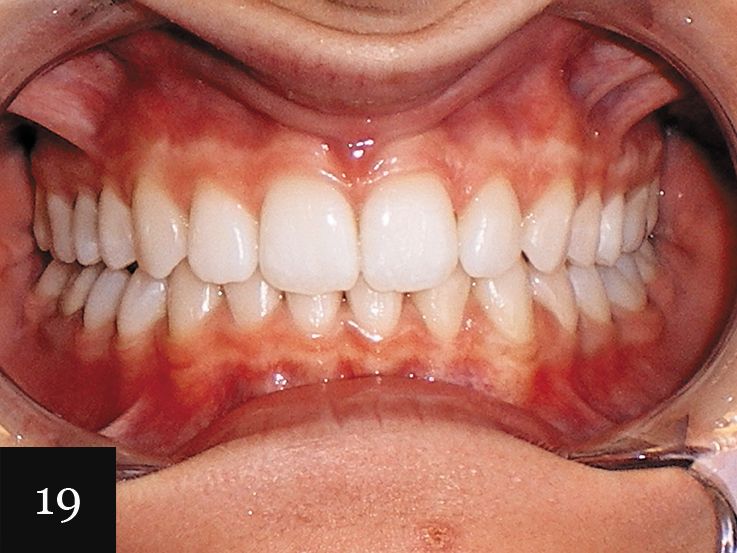

This case was performed on a patient in her late teens who presented with a very deep bite and severe crowding, as seen in Figs. 15-17.

The patient had consulted with multiple dentists who informed her that the lower lateral incisor would have to be extracted and that she was not a candidate for Invisalign. However, with an accurate impression we were indeed able to successfully treat this case with Invisalign, first using a series of 27 aligners, and then following up with an additional impression and eight more aligners for refinement (Figs. 18-20).